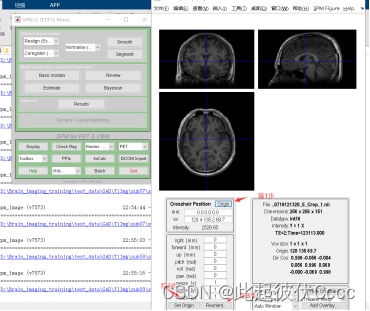

其中sub01_3DT1_20141225141440_5_Crop_1.nii文件便是我们后期需要处理的.nii文件,用mricron软件查看图像如下图所示:

2.2 检查图像,调整原点

首先就是需要我们自己手动调整一下结构像,打开spm,点击spm首页的PET&VBM,然后点Display,摆正每个被试的 T1 数据,并使 AC-PC 的连线水平。

手动将蓝色十字线的交叉点放到大概下面这个位置,即前联合的位置。